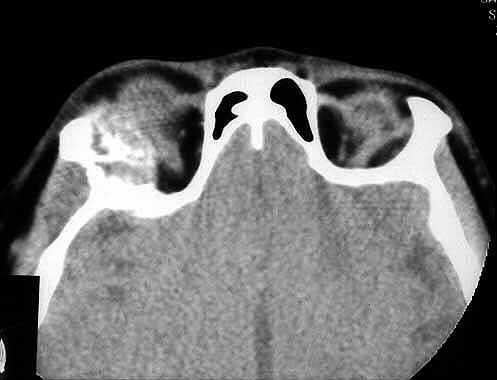

Fig. 1. CT sin contraste en la que se observa una lesión extraaxial en pared lateral de la órbita derecha y en fosa craneal anterior, con expansión del hueso afectado y afectación del interior de la órbita. |